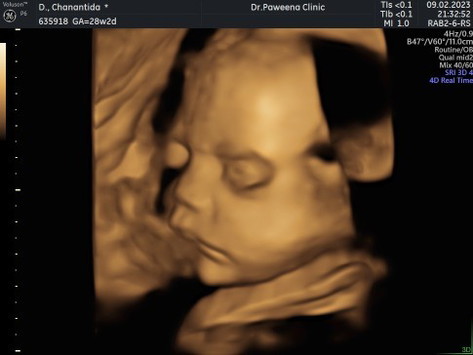

พอดีแม่ไปอัลตราซาวด์แบบ 4 มิติมาค่ะ ราคาโปรวันธรรมดา 1,500บาท คุณหมอจะปริ้นภาพให้ แล้วส่งไฟล์วีดีโอและรูปภาพเพิ่มเติมให้ทางไลน์เห็นหน้าน้องคือคล้ายกับลูกชายคนโตมากค่ะ กว่าจะได้ภาพดีๆแม่ต้องซาวด์ 2 ครั้ง เพื่อไปเดินไปทานน้ำเย็นให้น้องมีการเคลื่อนที่ น้องก็ยังเอามือเท้ามาบังหน้าอีกค่ะ แถมน้องดิ้นสุดๆๆ มือเท้าบังสุดๆๆ บ้านไหนเป็นแบบนี้บ้างไหมค่ะ